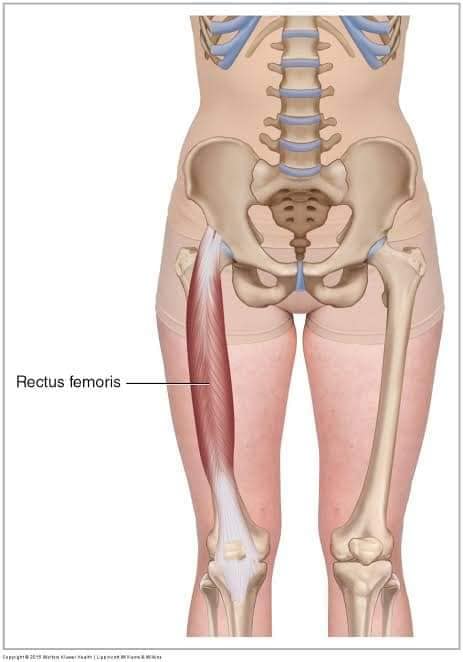

Скелетні м'язи з'єднані з кістками за допомогою сухожиль і відповідають за більшість волевих рухів. Вони поділяються на:

- Швидкі м'язи - призначені для швидких і потужних рухів.

- Повільні м'язи - забезпечують стійкі і довготривалі рухи.

Скелетні м'язи мають поперечну смугасту структуру, що забезпечує їхню здатність до швидкого і ефективного скорочення.